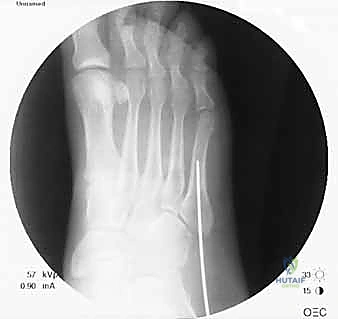

- التصوير بالأشعة السينية (X-rays): هي الخطوة الأولى والأساسية. يتم أخذ صور بأوضاع مختلفة (أمامية، جانبية، ومائلة) لتحديد موقع الكسر وشكله بدقة.

- الشق الجراحي الدقيق (Minimally Invasive): لا يقوم الدكتور هطيف بفتح شق كبير، بل يُحدث شقاً صغيراً جداً (حوالي 1 إلى 2 سم) عند قاعدة العظمة الخامسة لمشط القدم. هذا الشق الصغير يقلل من الألم بعد العملية ويسرع التئام الجرح ويحافظ على الشكل الجمالي للقدم.

- إدخال سلك التوجيه (Guide Wire): تحت توجيه الأشعة السينية المباشرة في غرفة العمليات، يتم إدخال سلك معدني رفيع جداً ليمر عبر الكسر وصولاً إلى النخاع العظمي. هذه الخطوة تتطلب دقة متناهية لضمان أن السلك في المنتصف تماماً.

- التحضير والتوسيع (Drilling/Tapping): يتم استخدام مثقاب خاص مجوف يمر فوق سلك التوجيه لتوسيع القناة النخاعية وتجهيزها لاستقبال المسمار.

- إدخال المسمار التيتانيوم (Screw Insertion): يتم اختيار مسمار طبي من التيتانيوم (طوله وسمكه محسوبان بدقة لتناسب عظمة المريض). يتم إدخال المسمار ليربط بين جزئي الكسر، مما يولد قوة ضغط (Compression) تجعل حواف العظم متلاصقة تماماً، وهو السر وراء الالتئام السريع.

- الإغلاق التجميلي: يتم إغلاق الشق الصغير بغرز تجميلية، ووضع ضمادة معقمة وحذاء طبي لحماية القدم.